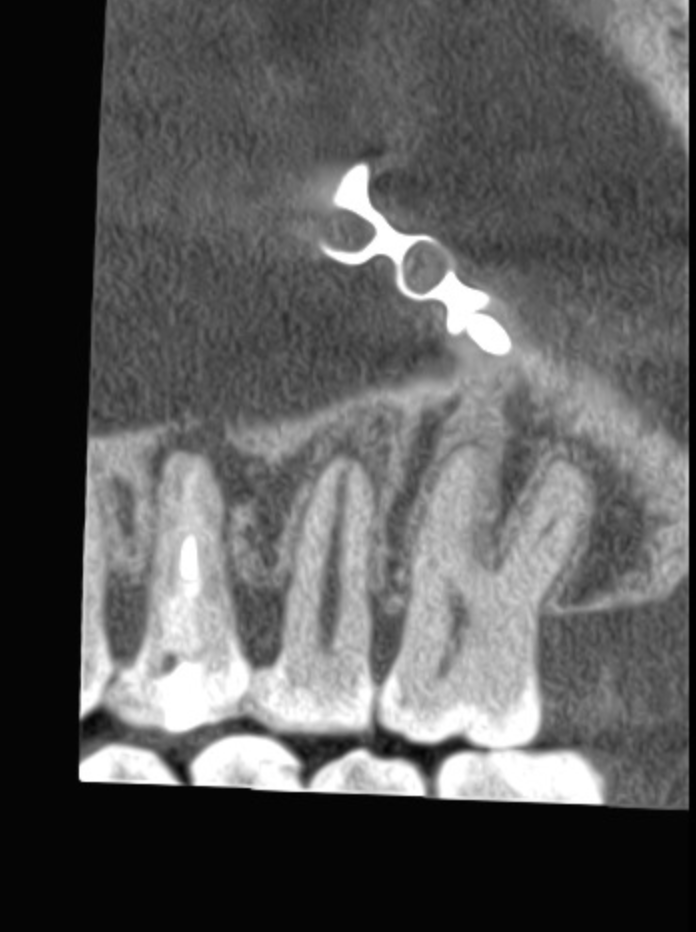

Vertical root fracture